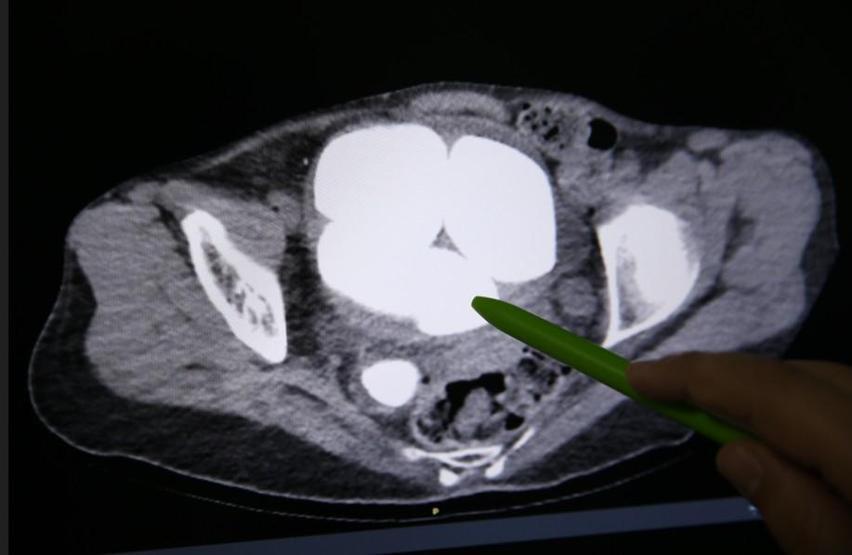

Hastanenin Üroloji Bölümü’nde Opr. Dr. Süleyman Çankaya tarafından yapılan incelemelerde, hastanın mesanesi ve idrar kanalında büyüklükleri 2 santimetre ile 9 santimetre arasında değişen 6 taş tespit edildi. Görüntüleme sonuçları, durumun sanılandan çok daha ciddi olduğunu ortaya koydu.

Uzmanlar, taşların yalnızca mesanede değil, sağ böbrek kanalında da bulunduğunu belirledi. Ayrıca yapılan değerlendirmede böbreklerde genişleme ve hasar bulgularına da rastlandı.